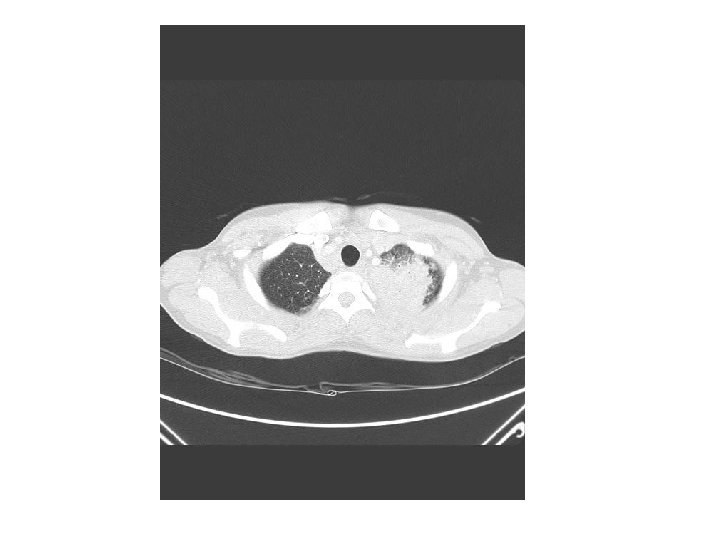

Femme de 36 ans • Consultation début avril 2011 • ATCD – Côte d’Ivoire – En France depuis mars 2011 – Veuve sans enfant, vit chez sa sœur – Fièvre typhoïde en 2009 • Fièvre, amaigrissement, arthralgies, dyspnée et toux • Séropositivité VIH 1

• Hospitalisation à Alençon • Examen physique peu contributif, petites adénopathies cervicales • Radiographie thoracique: pneumonie alvéolointerstitielle du sommet gauche • Hb= 6, 8 g/dl, GB= 4160/mm 3 (L=540/mm 3) • Lymphocytes CD 4= 45/mm 3 • ARN VIH= 494 340/mm 3 • Absence de mutation de résistance • BK crachats: BAAR (M. tuberculosis)